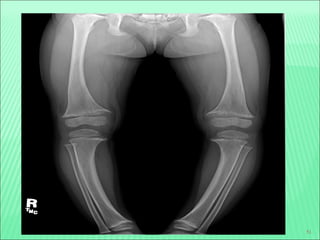

Bowleg deformity

X-ray in rickets

47 Knock knee deformity Wristenlargement Rib beading (rachitic rosary Harrison's sulcus and pot belly Chest deformity Frontal bossing Scoliosis X-ray in rickets